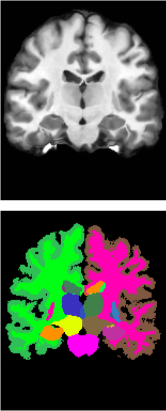

Evaluation Metrics. Due to the difficulty in acquiring manual landmark correspondences, for the T1-weighted (T1w) MR atlas to subject registration and T2-weighted (T2w) to T1w MR registration, we used the Dice similarity coefficient (DSC) as a surrogate measure to evaluate the accuracy of the registration. We first segmented all the scans using the deep learning-based whole-brain segmentation algorithm SLANT [38]. We report the mean label DSC between the warped segmentation and fixed segmentation over the segmented labels. To statistically evaluate the differences in DSC between VFA and each of the comparison methods, we employed the two-sided paired Wilcoxon signed-rank test (null hypothesis: distribution of the DSC differences is symmetric about zero). To measure the irregularity of the transformations, we report the number of non-diffeomorphic voxels (ND Voxels) computed using the central difference approximation of the Jacobian determinant. We also reported the non-diffeomorphic volume (ND Volume) [39], which measures the severity of the space folding under the digital diffeomorphism criteria.

Results. The performance of all the algorithms are summarized in Table 1 (left). VFA achieved the highest DSC among all algorithms with statistical significance (). We also report the effect size, calculated between the proposed method VFA and the comparison method with the highest mean DSC (Im2grid). The result further reinforces the superiority of VFA. Specifically, the Rank-Biserial Correlation (RBC) [46] was found to be , indicating a perfect positive relationship in the differences between paired observations. Additionally, the Common Language Effect Size (CLES) [47] was found to be , suggesting that there is a chance that a randomly selected pair will exhibit a difference in the expected direction favoring VFA. We also observed that VFA produced fewer folded voxels and smaller folded volumes compared with VXM, TransMorph, DMR, and PR-Net++ under the same choice of regularization weights . This behavior is likely related to the local search strategy adopted in the feature matching step, as evidenced by the similar results produced by Im2grid, which utilized a similar strategy. In contrast, TransMorph and DMR, which employed self-attention over a large window, did not exhibit this property. The smoothness of the displacement fields produced by each algorithm can be observed in Fig. 5. We also implemented a variant of VFA (VFA-Diff) with the addition of the scaling-and-scaling-technique. Both VXM-diff and VFA-diff demonstrated reduced folding compared to their original versions. We note that the scaling and squaring layer can be incorporated in all the algorithms shown in Table 1, although it cannot guarantee a perfect diffeomorphism due to the finite difference approximation of the Jacobian computation [39].

Results. The performance of all the algorithms are summarized in Table 1 (right). Since inter-modality registration is a more challenging task than intra-modality registration, there is a decrease in registration accuracy for all algorithms. Nevertheless, VFA achieved the highest DSC among all algorithms with statistical significance (). We also report the effect size, calculated between the proposed method VFA and the comparison method with the highest mean DSC (DMR). The Rank-Biserial Correlation (RBC) [46] was found to be and the Common Language Effect Size (CLES) [47] was found to be . Sample results are shown in Fig. 5.